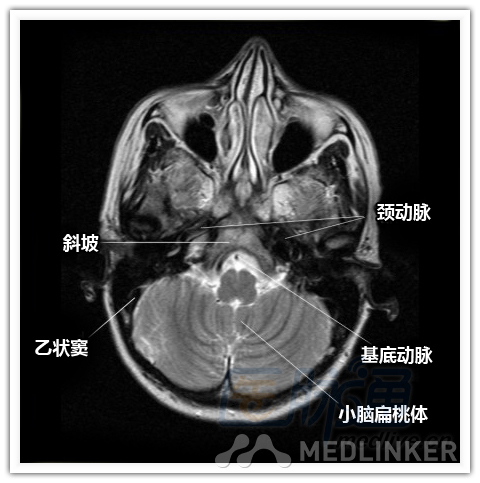

简明易懂的脑部断层解剖:横断位MRI(1)

本文将对不同横断位的脑部MRI图像进行标示,主要讲解内容是脑部基本解剖。脑部横断位解剖,尤其是内囊层面的影像学解剖一直是一大重点,一起来学习一下。 横断位图像顺序:由足侧至头侧 本文转载自医脉通。 声明:本文转载是出于提供更多信息以参考使用或学习、交流之目的,不用于商业用途。转载无意侵犯版权,如转载文章涉及您的权益等问题,请作者速来告知,我们将尽快做删除处理。